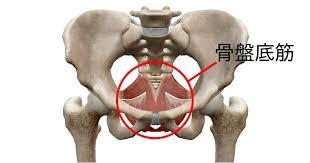

骨盤底筋(こつばんていきん)

腰周りの下の部分を覆うように付いています。

この筋肉が落ちると「尿漏れ」の原因になると言われています。

60を過ぎると増えてくる症状ですので注意が必要です。